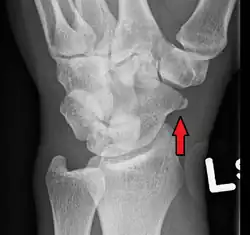

An X-ray showing a fracture through the waist of the scaphoid

A scaphoid fracture is a break of the scaphoid bone in the wrist.[1] Symptoms generally includes pain at the base of the thumb which is worse with use of the hand.[2] The anatomic snuffbox is generally tender and swelling may occur.[2] Complications may include nonunion of the fracture, avascular necrosis of the proximal part of the bone, and arthritis.[2][1]

Scaphoid fractures are most commonly caused by a fall on an outstretched hand.[2] Diagnosis is generally based on a combination of clinical examination and medical imaging.[2] Some fractures may not be visible on plain X-rays.[2] In such cases the affected area may be immobilised in a splint or cast and reviewed with repeat X-rays in two weeks, or alternatively an MRI or bone scan may be performed.[2]